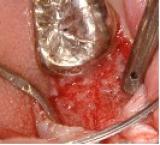

GTR (歯周組織再生) | |||||||||||

| 歯槽膿漏でなくなった歯周組織を再生することをGTRといいます。 |

![]() |

【術前】 |

【術後】 |